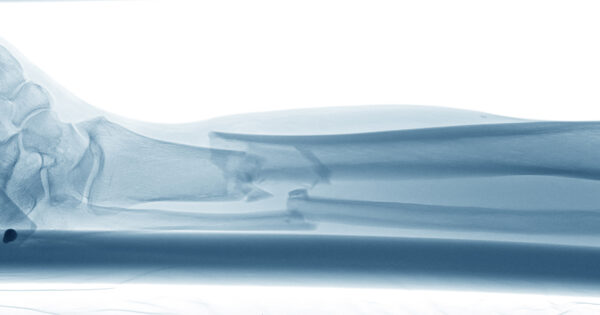

အရိုးကျိုးခြင်းသည် အကြောင်းအမျိုးမျိုးကြောင့် ဖြစ်ပွားနိုင်သည်။ အနည်းဆုံးထိုးဖောက်အရိုးပြုပြင်ခြင်းနည်းပညာများ သို့မဟုတ် မြေအောက်ရထားအရိုးကျိုးခွဲစိတ်မှုသည် လူနာများအား ၎င်းတို့၏ပုံမှန်ဘဝသို့ ပြန်လည်ရောက်ရှိစေရန် ကူညီပေးသည်။